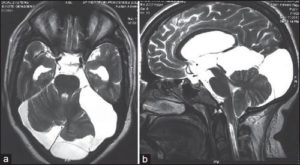

Картина арахноидальных изменений ликворокистозного характера в ходе исследований МР и КТ показывает наличие очагов с плотностью цереброспинальной жидкости, что подтверждает кистозную, неопухолевую природу образования.

В ходе инструментального исследования чаще наблюдается расширение желудочков и экстрацеребральных (изолировано расположенных в мозге) пространств, содержащих ликвор. Электроэнцефалография проводится до и после оперативного вмешательства. Во втором случае с целью определения результатов лечения и правильного подбора противосудорожных препаратов.

На МРТ головного мозга арахноидит чаще всего не имеет достоверных признаков, но иногда может приводить к формированию кист, расположенных в субарахноидальном пространстве, то есть между мозгом и костью черепа. Это так называемые арахноидальные кисты. Арахноидальные кисты имеют четкие признаки на МРТ. Но, к сожалению, чаще всего мы не можем сказать, возникли эти кисты вследствие арахноидита, или они имеют врожденный характер. Поэтому в современной неврологии понятия «арахноидит» и «арахноидальная киста» различаются, и путать их не стоит.

Основным методом ее диагностики является МРТ. На снимках арахноидальные изменения ликворокистозного характера выглядят как образования темного цвета, с четко ограниченными контурами, чаще всего округлой формы.